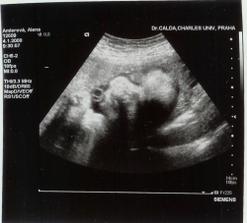

9.11.2007 jsme byly na biometrii a mame cca 952g -----

21.11.2007 jsme byly na 3D,4D UTZ mame cca 1296g a malá vůbec nespolupracovala proste spala ----- 4.1.2008 tak mame cca 2001g ----- 18.1.2008 kontrola dopadla dobře otvirame se jak máme ----- 25.1.2008 další kontrola -----tak kontrola se nekonala misto ni se narodila mala v 37+6tt v 6:17 vážila 2520g a měřila 46cm ____________________________________________________________________________________________________________________________________________________